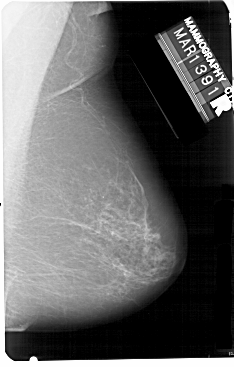

A_1341_1.LEFT_CC

LEFT_CC LINES 5491 PIXELS_PER_LINE 3151 BITS_PER_PIXEL 12 RESOLUTION 43.5 OVERLAY

FILE: A_1341_1.LEFT_CC.OVERLAY

TOTAL_ABNORMALITIES 1

ABNORMALITY 1

LESION_TYPE MASS SHAPE ROUND MARGINS ILL_DEFINED

ASSESSMENT 4

SUBTLETY 4

PATHOLOGY BENIGN

TOTAL_OUTLINES 1

BOUNDARY